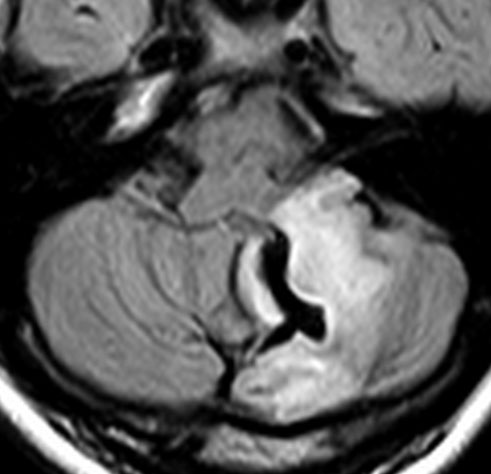

小脳毛様細胞性星細胞腫のFLAIR画像所見

壁在結節を伴うのう胞性小脳毛様細胞性星細胞腫は,結節を手術摘出すれば治癒するものです。しかし,あたかも腫瘍が残っているようなMRI画像所見が残ることがあります。

この例は,10歳の子どもに無症状で偶然発見された大きなのう胞性小脳毛様細胞性星細胞腫です。開頭手術で腫瘍結節は全摘出して腫瘍のう胞は縮小したままです。(画像はクリックすると拡大して見えます)

開頭手術で白く増強される結節部分だけを摘出しました。MIB-1はやや高値で3%と報告されました。病理組織診断は,WHO grade 1 毛様細胞性星細胞腫です。

6年後のMRI FLAIR画像です。摘出腔周囲の高信号域が残存しています。ここまで残ると腫瘍周辺浮腫ではありませんし,腫瘍細胞が左小脳半球に広範囲に浸潤して残存しているものだと判断されます。しかし,6年間で病変の増大傾向がありませんでした。この残存腫瘍(らしい所見)に対して放射線治療や化学療法を行うべきかどうか,結論は出ていません。しかし,経過観察を続けても増大して来ない例があることは確かです。一方で,この高信号領域が拡大したり,ガドリニウム増強される病変が再出現して治療がまた必用となることもあります。